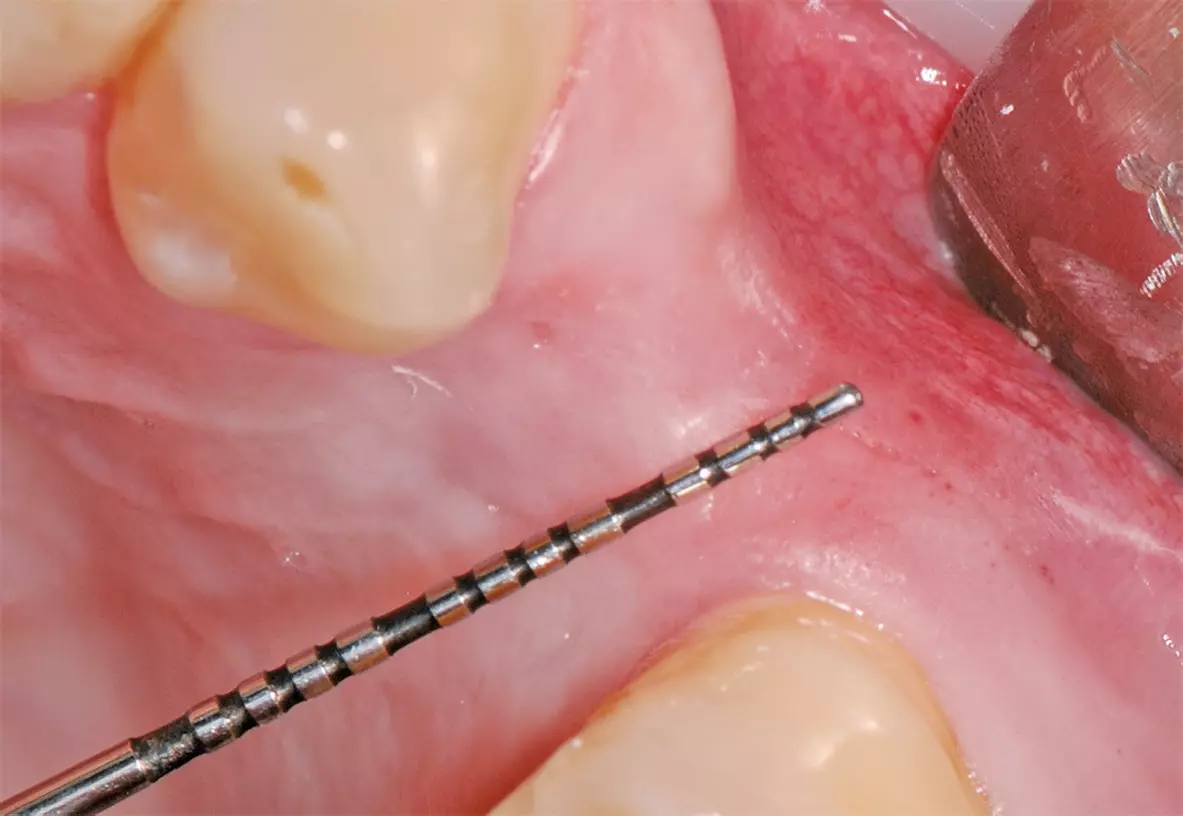

Nach schonender Extraktion des Zahnes 24 unter Erhalt der vestibulären Lamelle wurden die PRF-Plugs in die Extraktionsalveole eingebracht (Abb. 14 und 15) und mit einer Naht fixiert (Abb. 16). Am ersten postoperativen Tag zeigte sich die Wunde reizlos und Fibrinbelegt (Abb. 17). In der ersten postoperativen Woche war die Patientin beschwerdefrei und hatte nicht von ausgeprägten Schwellungen oder Schmerzen berichtet. An Tag 7 war die Wunde vollständig geheilt und mit gesunder Gingiva überdeckt. Eine leichte Mulde von etwa 1 mm war noch zu beobachten (Abb. 18). Nach drei Monaten zeigten sich gesunde Weichgewebsverhältnisse, sowie ein weitgehend erhaltener Alveolarkamm mit leichter vestibulärer Einziehung (Abb. 19).

Ein Implantat konnte erfolgreich in regio 24 mit einer ausreichenden Primärstabilität inseriert werden (Abb. 20). Nach drei Monaten wurde das Implantat freigelegt (Abb. 21) und anschließend mit einer Krone versorgt (Abb. 22).